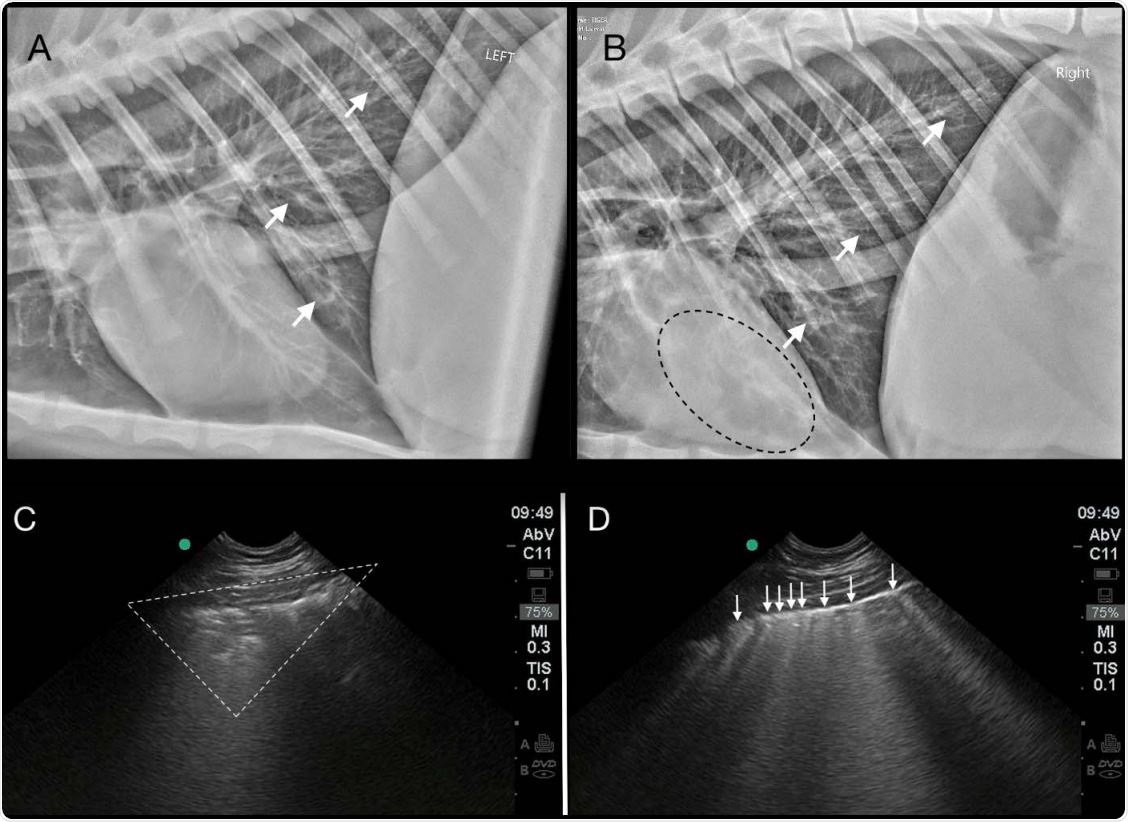

This tissue damage, along with signs of respiratory disease and a “white lung” appearance, is consistent with the imaging results reported for infected humans, say Bartlett and colleagues.

Thoracic imaging abnormalities in the index Tiger (T1) with SARS-CoV-2 infection. A generalized bronchial pattern with peribronchial cuffing and bronchiectasis (white arrows) is present in the caudal lung on left lateral (2A) and right lateral (2B) radiographs. Anesthesiaassociated atelectasis is seen as an alveolar pattern superimposed over the heart (black dotted line) (2B). Pulmonary ultrasonography reveals peripheral consolidation (white dotted triangle) (2C), and coalescence of vertical B-lines (white arrows) (2D) indicating AIS (alveolar-interstitial 580 syndrome).